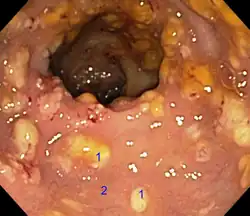

Тревожные симптомы, к которым относится прежде всего появление крови в кале, — основание для колоноскопии, то есть визуального исследования внутренности толстой кишки с помощью эндоскопа. Его трубка снабжена осветительным устройством и миниатюрной камерой, передающей изображение на большой цветной монитор. Применение эндоскопа позволяет осмотреть всю внутреннюю поверхность толстой кишки. В случае выявления мелких полипов их можно удалить, избежав злокачественного развития.